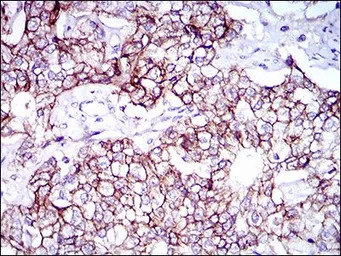

IHC-P analysis of bladder cancer tissue using GTX60798 CD166 antibody [4H9A5].

IHC-P analysis of prostate cancer tissue using GTX60798 CD166 antibody [4H9A5].